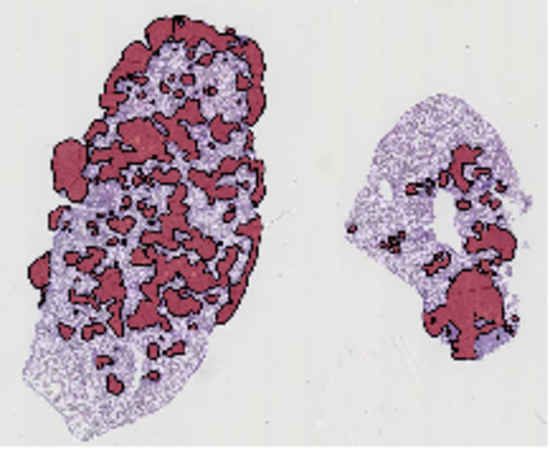

Self-training algorithms for exploiting sparse annotations (Mormont et al., ECCV AIMIA 2022) and algorithms for the quantification and delineation of tissue areas in whole tissue slides (Marée et al. ISBI 2014).